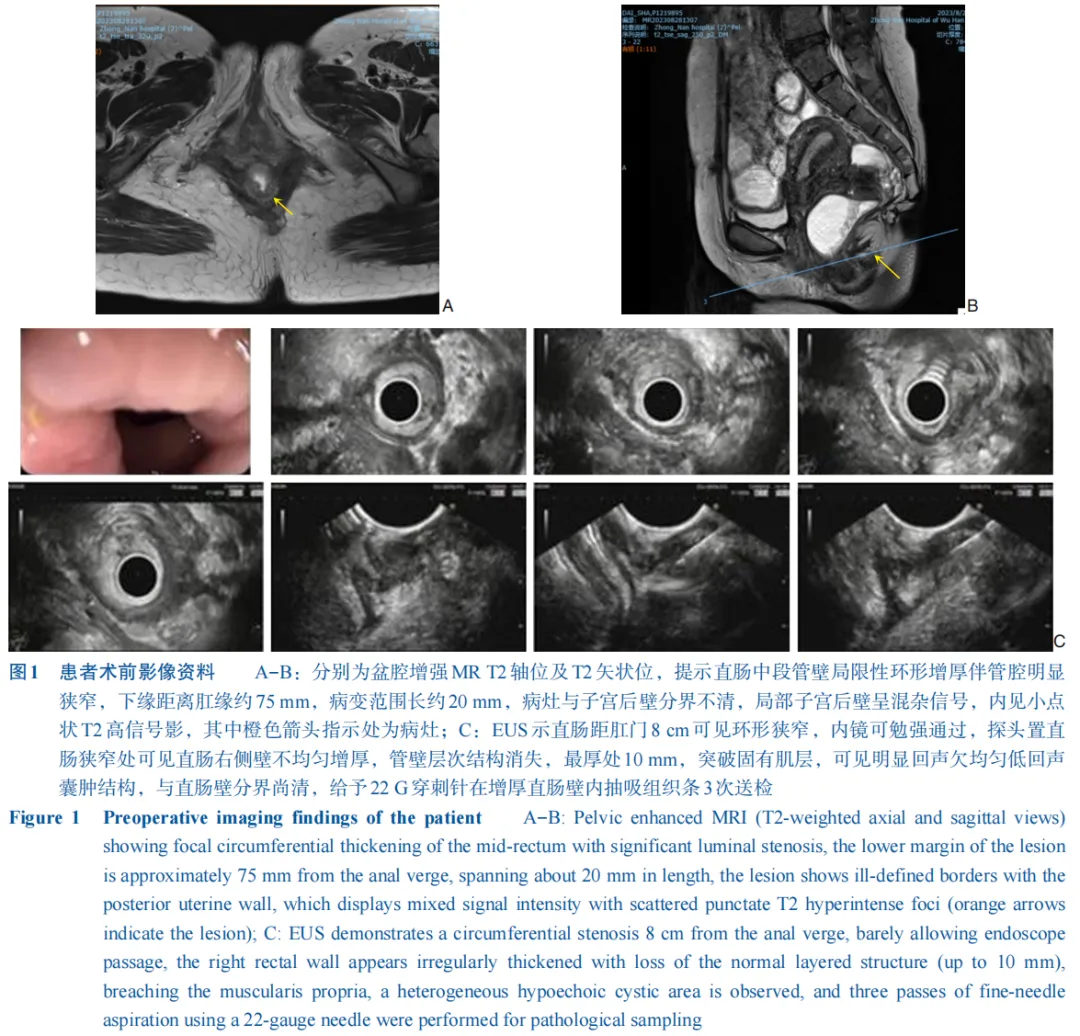

武汉大学中南医院多学科诊疗团队分享1例直肠深部浸润型子宫内膜异位症(DIE)患者的完整诊疗历程,突出了以结直肠肛门外科为主导、联合妇科与泌尿外科的多学科诊疗(MDT)协作模式,不仅实证了EUS-FNA作为DIE早期诊断关键工具的价值,弥补了传统影像与活检的局限性,更通过MDT实践彰显了多学科整合在提升手术根治性、优化患者预后方面的示范作用,为复杂盆腔疾病个体化诊疗提供了前沿范式,紧密契合精准医疗与跨学科协作的当代趋势。